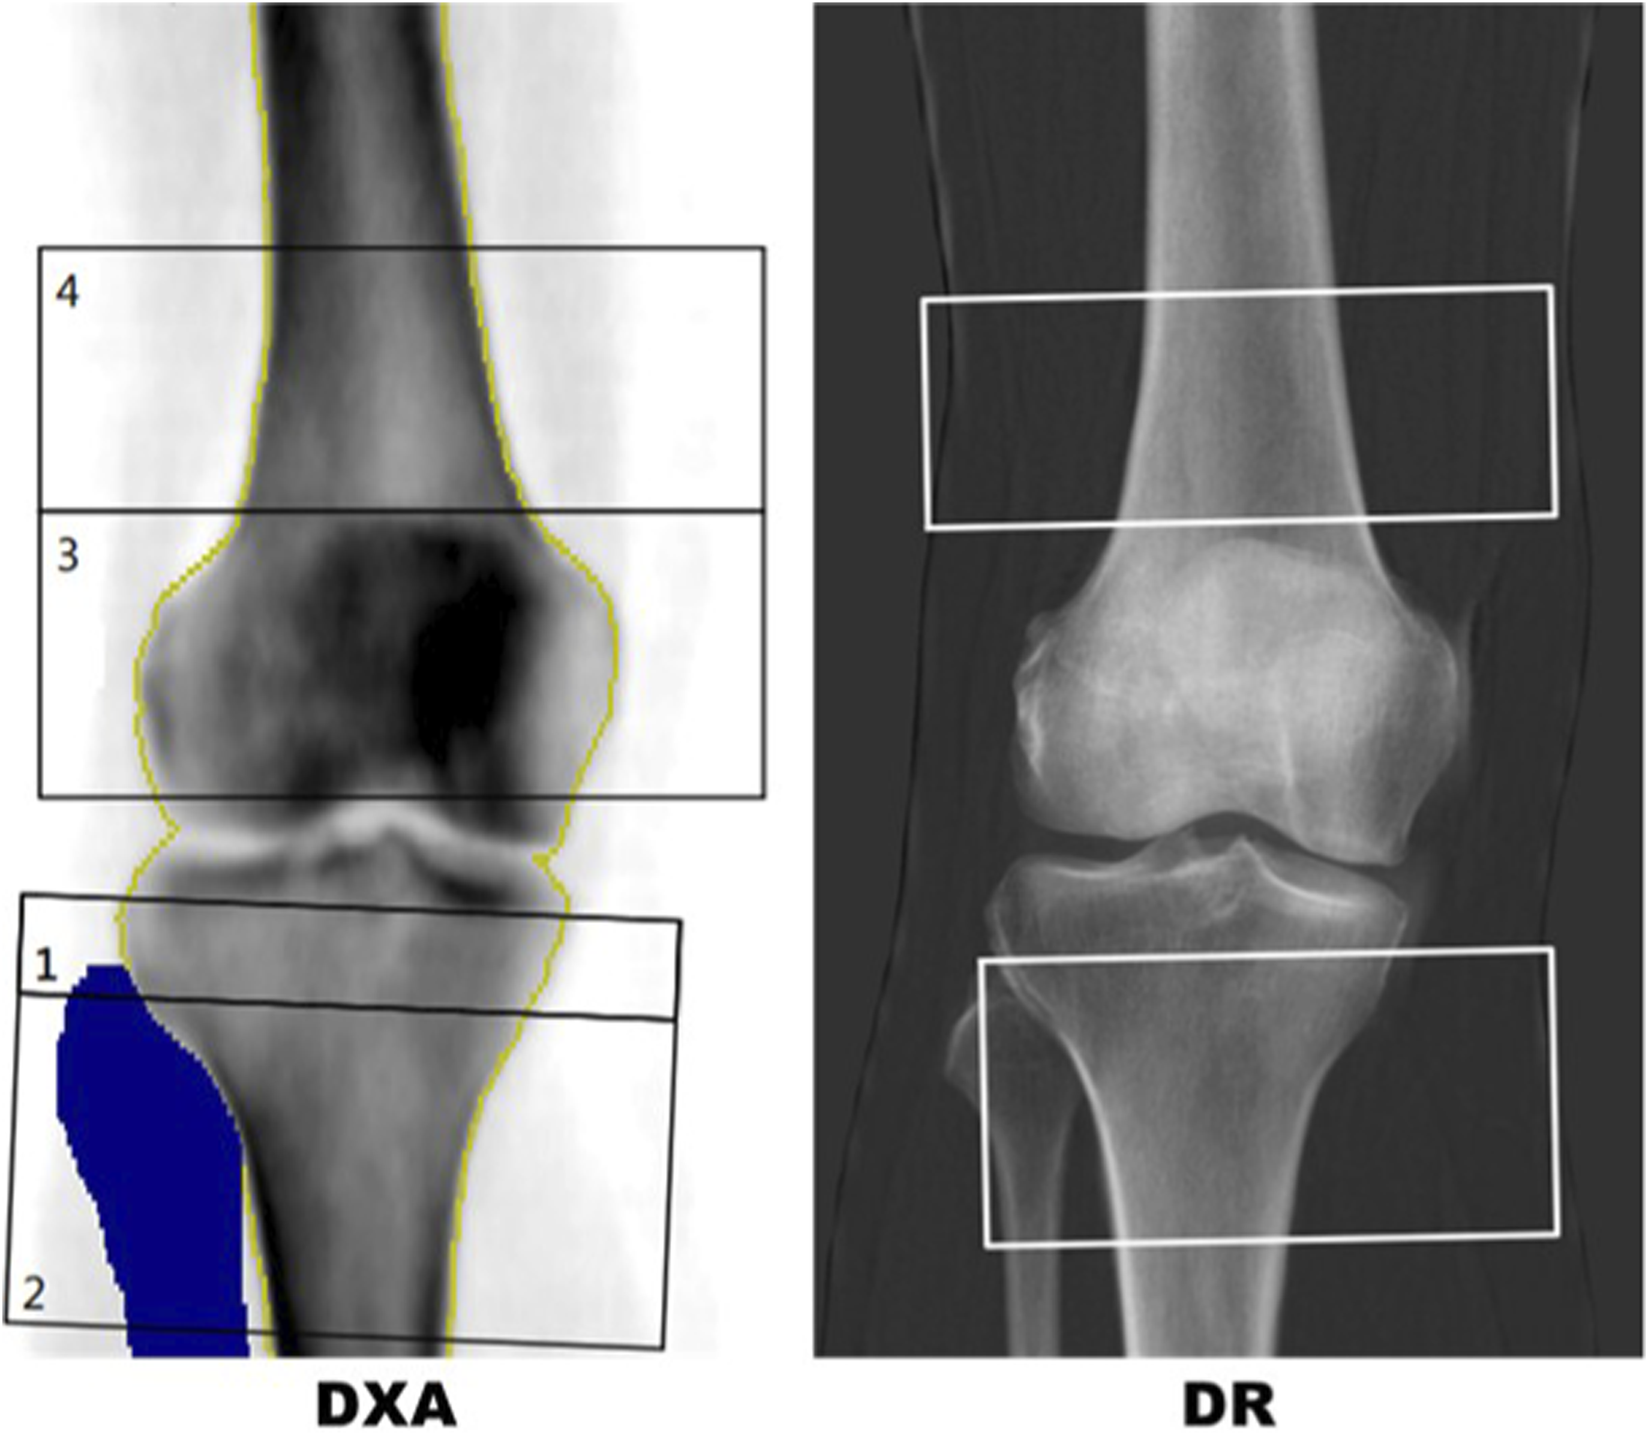

DXA analysis at the knee utilised a bespoke template for ROI placements (see Figure 2) designed to avoid superimposition from the patella and any sclerotic changes relating to the tibial joint surface. Two ROIs for measurement of aBMD and T-score were defined for the AP knee DXA scans. The PT ROI was defined as a 50 × 100 mm rectangle centred 40 mm in the inferior direction from the midpoint of the tibial plateau. The fibula bone was removed from the DXA analysis. The DF ROI was defined as a 40 × 110 mm rectangle centred some distance superior to the intercondylar fossa. This distance varied per scan and was defined as the height of the patella. Three blinded researchers carried out an inter-operator precision exercise for knee DXA, post-processing 10 cases, three times each, resulting in a Root Mean Square Coefficient of Variation of 1.39% for PT and 1.18% for DF analysis of aBMD.

FIGURE 2

Left: DXA report with template for distal femur (box 4) and proximal tibia (box 2). The blue region is a mask for the fibula showing the region that has been removed from the proximal tibia region of interest (ROI). Right: IBEX BH bone density image with semi-automated distal femur and proximal tibia boxes.

In DR scans, segmentation masks of the femur, tibia, fibula and patella were used to replicate the DXA procedure in a semi-automated approach. The masks were manually labelled by a team of labellers but an automated machine vision algorithm was used to identify the ROIs using the segmentation of the femur, tibia, fibula and patella. A comparison of typical DR and DXA ROIs for the same patient are shown in Figure 2.